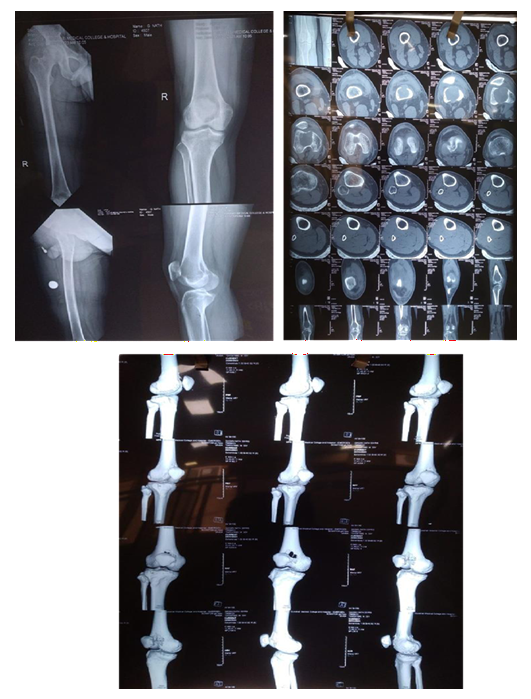

CASE 1

Diagnosis established with

MRI

Biopsy

Pre Denosumab Therapy: Break in the cortex can be clearly seen

After Neoadjuvant Denosumab Therapy

Operative Intervention

Histopathology

Followup